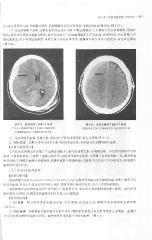

Page 313 - 医学影像诊断学